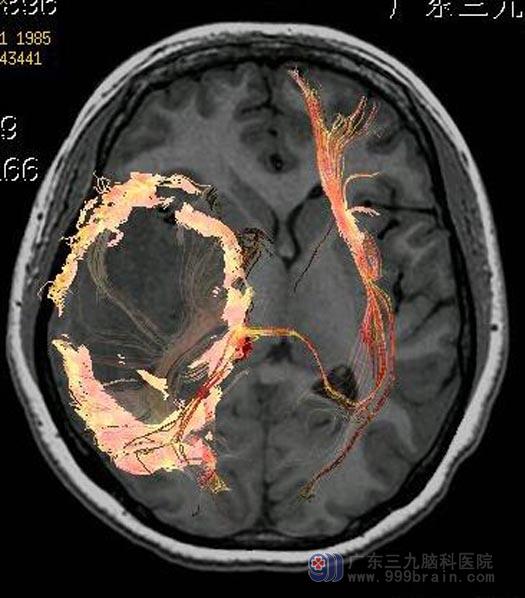

术前DTI

岛叶胶质瘤属于脑深部的肿瘤,以低级别为主,由于不在大脑表面,而且有大脑中动脉及其分支走行其表面,手术难度非常大,因其解剖的特殊性,要想多切一些,就必须在血管缝隙里一点一点地把肿瘤掏出来。虽然可以使用包括唤醒麻醉、术中超声、神经导航,诱发电位和皮质电刺激等先进的辅助技术和技巧,岛叶胶质瘤的切除对于神经外科医师仍然是一个不小的考验。

深入的检查、讨论、研究后,鲁明主任主刀唤醒麻醉下行右侧颞岛叶胶质瘤切除术。术前根据导航定位肿瘤,术中唤醒病人,利用荧光造影,在显微镜下切除肿瘤。手术中小艺的肢体、语言活动良好,手术过程顺利。术后小艺神志清醒,肢体活动良好,正积极接受术后治疗,待进一步康复出院。